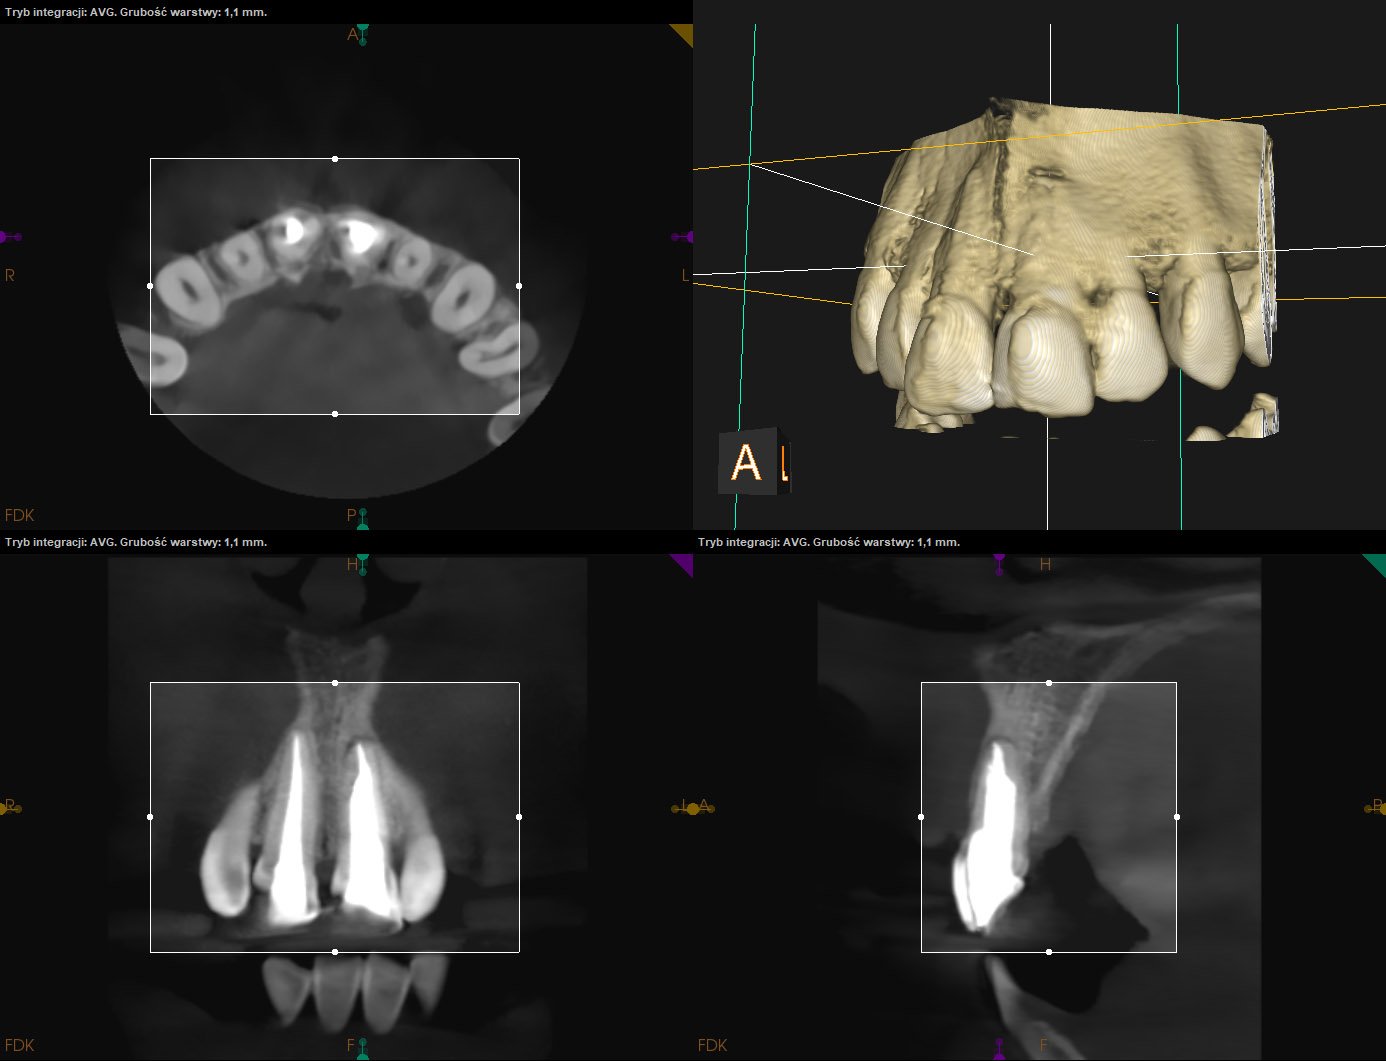

CASE STUDY V

Reendo d.26. Wykonano ponowne leczenie kanałowe systemu korzeniowego z odnalezieniem i udrożnieniem pominiętego przy pierwotnym leczeniu kanału MB2 (anatomicznie typ VI w klasyfikacji Vertucciego).